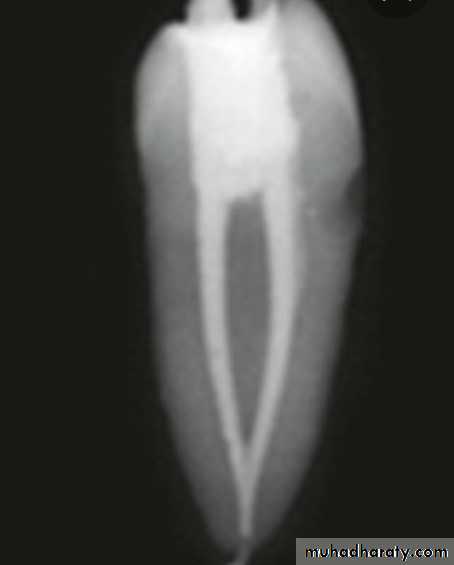

• Do not adhere to dentin.

Gap location between gutta percha and the root dentin